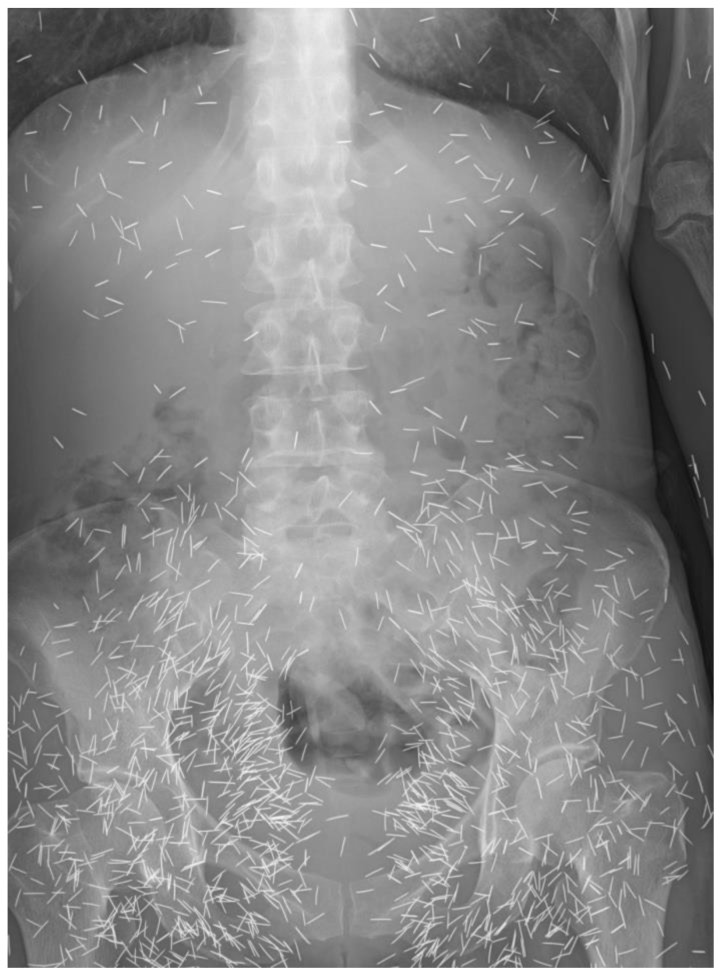

Если всё же продолжаете сомневаться и бояться, то предлагаю ознакомиться с Малазийской культурой сусук, где иглами буквально начиняют всё тело в каких-то метафизических целях, и при этом живут себе спокойно. Мало того, они даже ждут удачу от этих самых иголочек. Предлагаю ознакомиться конкретно с этой заметкой – [19]

Вот случай, который был у нас в отделении. Поступила пожилая женщина с тремя иглами в животе, которые находились там так давно, что были уже с признаками коррозии.